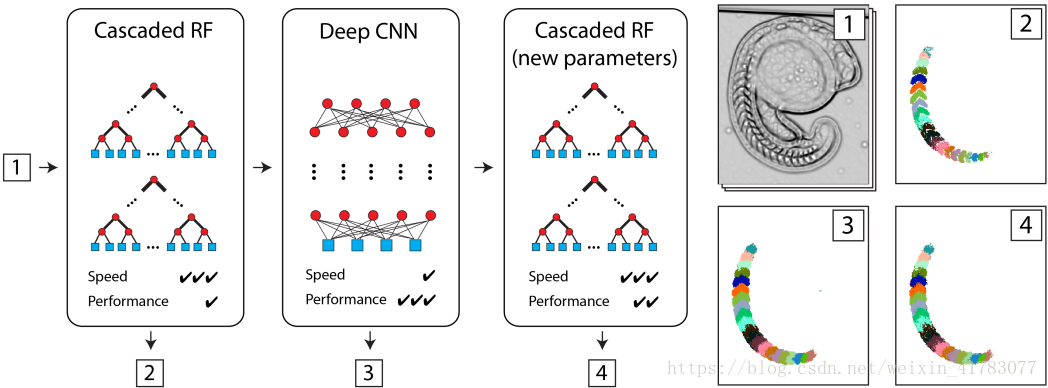

而文献[42]提出了级联的随机森林和卷积神经网络相结合的模型,在这个模型中结合了级联的随机森林执行速度快和卷积神经网络性能好的优势,并且有两种结合方式。一种方式利用随机森林容易训练的特点,训练好的随机森林模型作为卷积神经网络的初始化,这样会大幅较少卷积神经网络模型的训练时间。另一种方式将训练好的卷积神经网络模型映射到级联的随机森林模型,在保持级联的随机森林能有快速推理性能不变的情况下提高分割的准确率,该模型如图17所示。

(a) (b) (c) (d)

图17 (a)级联RF训练预测密集的语义标签。(b)级联RF然后映射到一个卷积神经网络,并进一步训练,以提高性能。(c)最后,卷积神经网络被映射到一个级联RF更新参数,以改善在测试时的速度。(d)三个分类器在斑马鱼胚胎显微图像语义分割中的应用:输入滤波器组(d1)和相应的分割输出(d2-d4)。